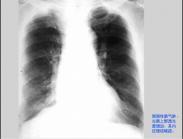

肺氣腫(emphysema)系終末細支氣管遠端部分(包括呼吸性細支氣管、肺泡管、肺泡囊及肺泡)過度膨脹,并伴有氣腔壁的破壞。1987年美國胸科學會(ATS)對肺氣腫的定義作了修訂:“終末細支氣管遠端部分有不可逆性擴張伴有肺泡壁的破壞,但沒有明顯的纖維化”。肺氣腫的基本特征性是換氣部分的肺組織過度充氣和氣流阻塞,所以稱之為“阻塞性肺氣腫”(obstructive pulmonary emphysema)。